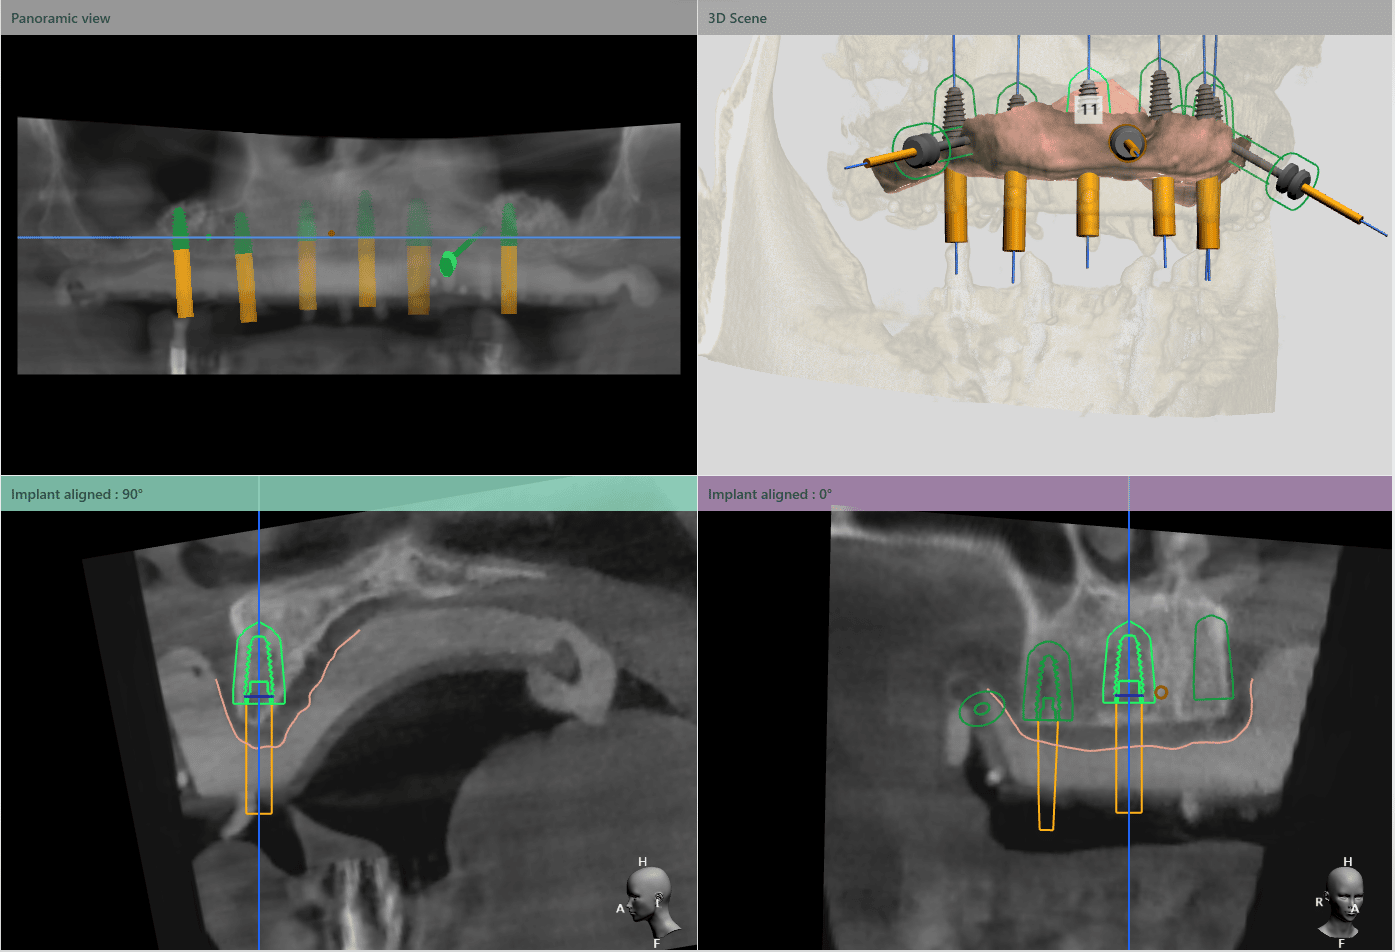

Medicul specialist a efactuat scanarea digitală a arcadelor pe care a trimis-o tehnicianului dentar DigiRay, împreună cu CBCT-ul pacientului.

Odată planficată și agreată poziția și axul de inserție al fiecarui implant, tehnicianul DigiRay efectuează designul șablonului chirurgical și printarea acestuia dintr-o rășină bio-compatibilă.

Ulterior, tehnicianul editează protocolul și secvența de frezare conform sistemului de implanturi și trusei chirurgicale folosite de către medic și îl trimite prin email medicului curant.